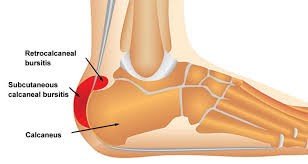

Image showing retrocalcaneal bursitis

- Bursae are small, fluid-filled sacs that reduce friction between bones and soft tissues. Bursitis occurs when these sacs become inflamed due to repetitive stress, poor footwear, or trauma.

- Symptoms include localized swelling, redness, tenderness, and pain, especially during walking or ankle movement.

- Common sites for bursitis in the ankle include the retrocalcaneal bursa (near the Achilles tendon) and the lateral malleolus (outer ankle)